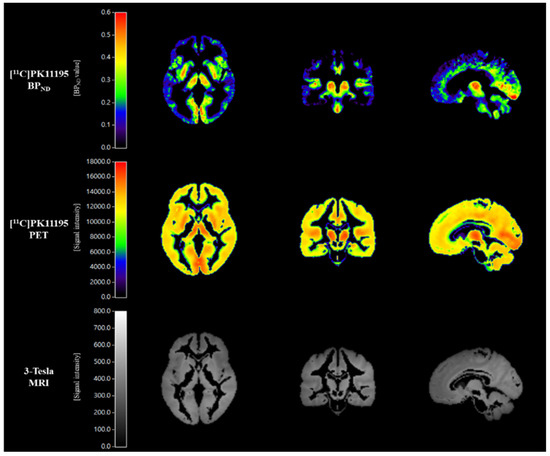

2.4. [11C]PK11195 PET Imaging Analysis

Figure 1. Representative mean images of [11C]PK11195 BPND, [11C]PK11195 PET, and corresponding 3-Tesla MRI in the control group.